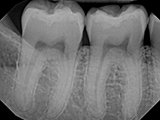

| X-Ray Example |

X-ray taken with the Schick 33 Sensor |

Dental X-Ray Comparison

X-ray taken with the Schick® 33 sensorCarestream